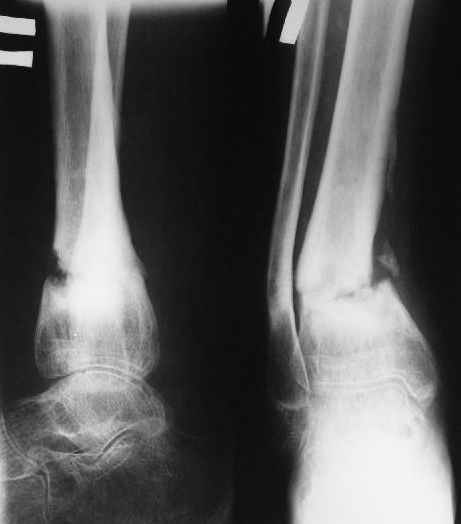

В январе 2005: варусная деформация н\3 голени, болевой с-м, комбинированная контрактура г\стопного сустава, нейропатия м\берцового нерва сохраняется слабость разгибания 1 пальца.

Операции: 1 Клиновидная резекция на вершине деформации м\берцовой кости.

2 Тугоподвижный ложный сустав н\3 б\берцовой кости. Рубцы выполняющие пространство между отломками, канал проксимального отломка иссечены.

Одномоментное устранение деформации, остеосинтез Г-образной пластиной.

Пластика по Хахутову.

Фиксация

|

в гипсе